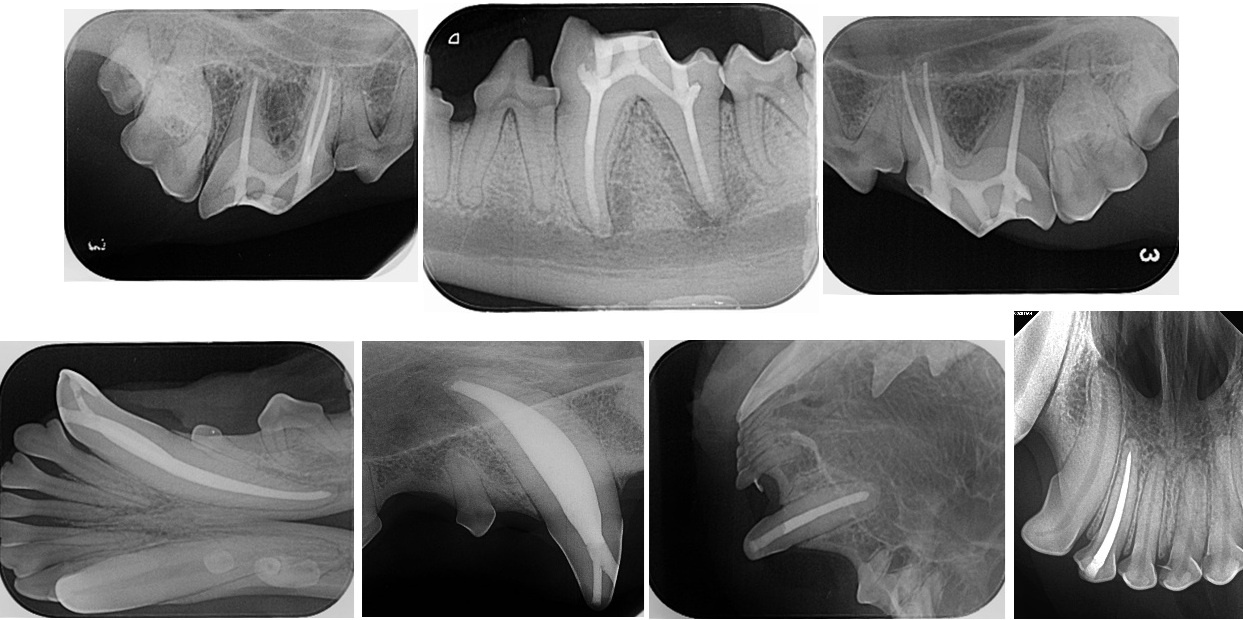

현재 수의치과학에서의 근관치료는 사람의 근관치료를 위해 개발되고 발전해 온 기구와 재료를 사용할 수밖에 없는 현실에 놓여 있다. 그러나 사람과 개, 고양이의 근관 해부학적 특성은 분명히 다르다. 따라서 이러한 기구와 재료를 개와 고양이의 근관 해부학에 맞게 적절히 변형(modification)하여 적용하는 것이 중요하다. 특히 사람에 비해 훨씬 복잡한 apical delta가 발달한 개와 고양이에서는 근단 1/3 부위를 얼마나 효과적으로 성형·세정·충전하는지가 높은 성공률을 좌우한다는 점이 최근 발표된 여러 문헌을 통해 확인되고 있다.